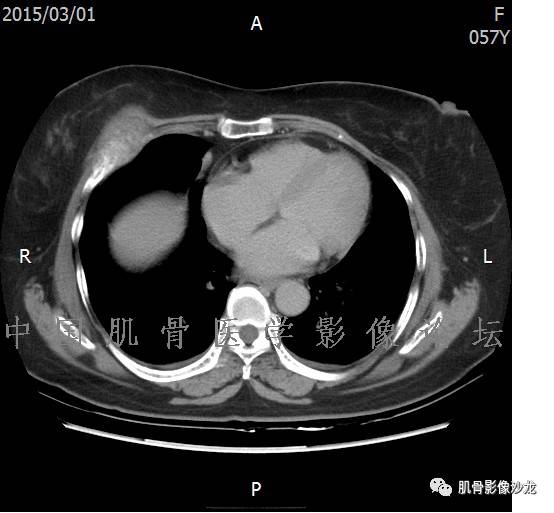

患者于2月前无明显诱因下出现腰骶部疼痛,夜间为重,逐渐加重伴左下肢麻木、疼痛,并有行走活动受限,在我院就诊,摄腰椎及骶髂部CT提示:腰椎骨质退变,腰3-4、4-5椎间盘膨出,骶髂关节炎。自用非甾体抗炎药无好转,再次来院就诊,门诊拟“骶髂关节炎”收住我科。病程无间歇性跛行,大小便正常。

专科检查:神清,脊柱无侧弯后凸畸形,椎体各节段无压、叩痛,双侧棘突旁无压痛,双侧骶髂关节压痛明显,左下肢放射痛,浅感觉较健侧减退,腰椎前屈后伸活动受限,膝、跟腱反射正常。

辅助检查:腰椎及骶髂部CT提示:腰椎骨质退变,腰3-4、4-5椎间盘膨出,骶髂关节炎。

雪舞 :第二例,位于骶骨,有骨质破坏并有软组织肿块,软组织肿块边界清

雪舞 :第二例挺难的,骨质破坏是溶骨性的,局部皮质中断,软组织肿块外缘光滑